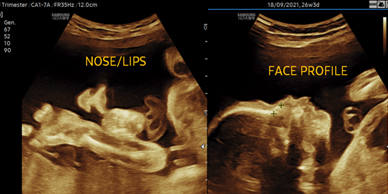

Skanda Advanced Ultrasound Scan Centre starts right from the onset of pregnancy. Our Fetal Medicine experts are concerned with the health of the fetus at every stage – monitoring growth & development; predicting, detecting & managing any complications; and treating congenital disorders & anomalies in the womb itself.